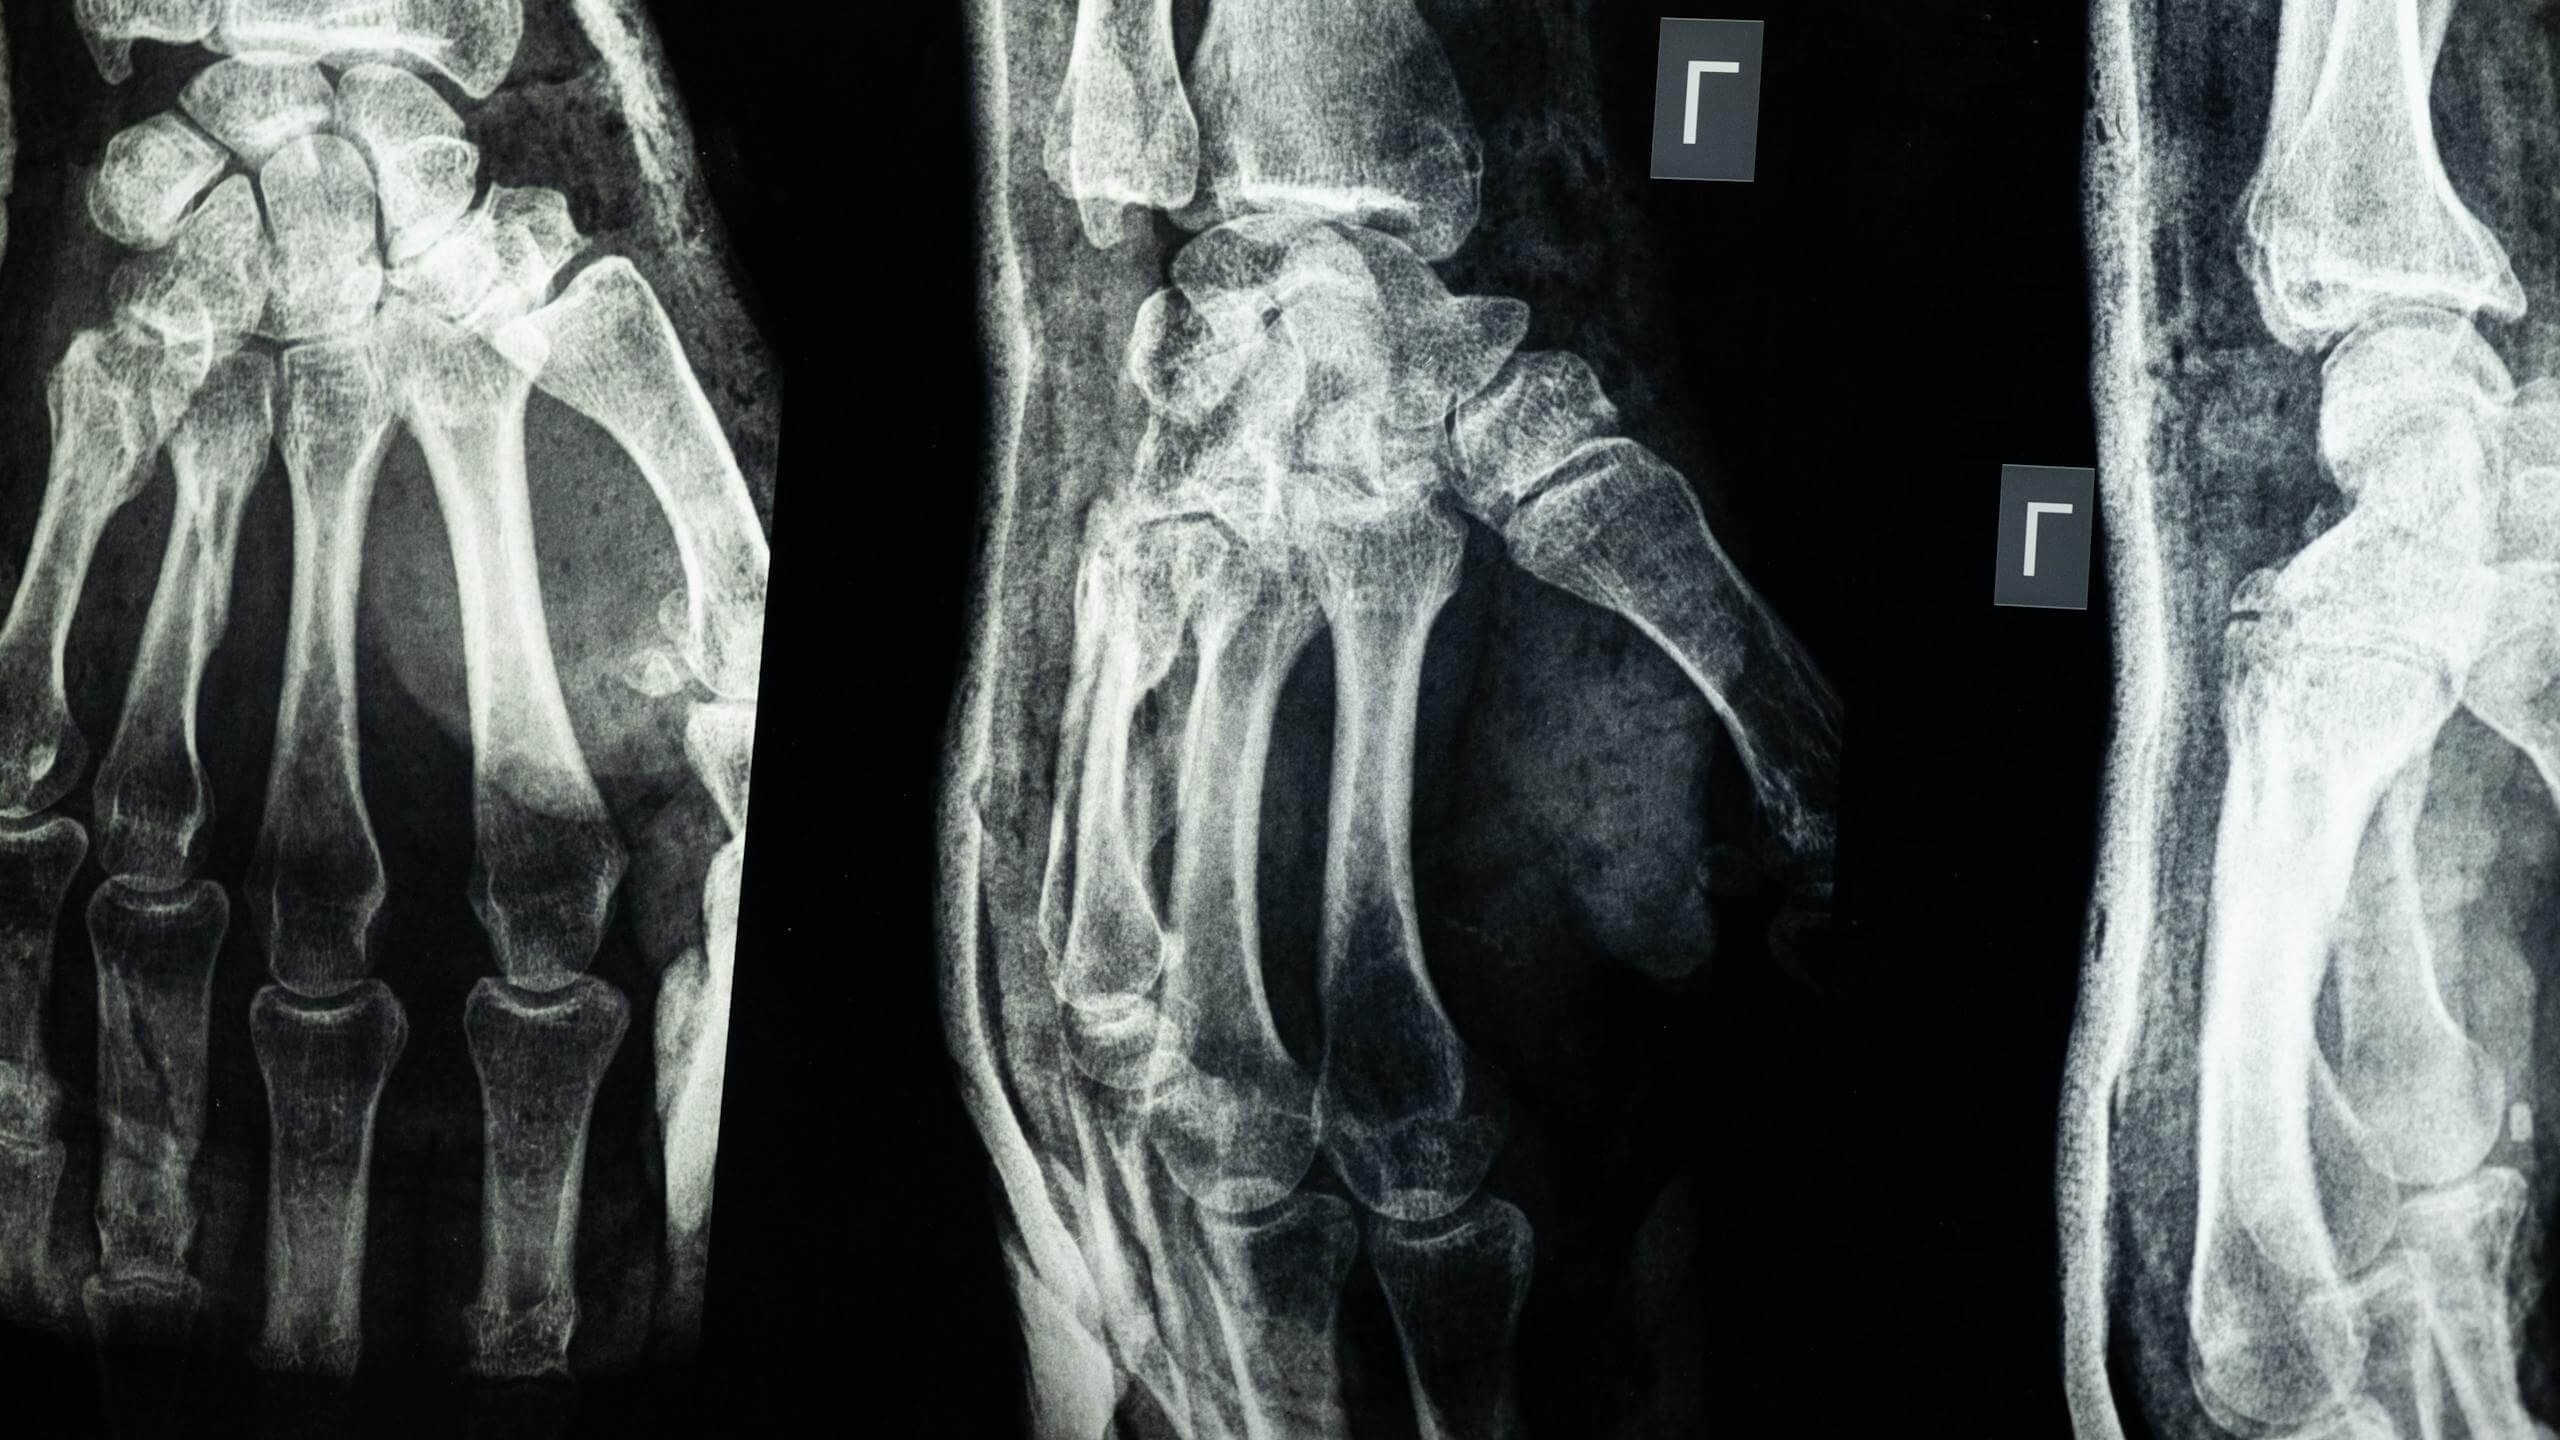

Fu in quel preciso istante che nacque un nuovo modo di pensare la materia: Röntgen intuì la presenza di radiazioni ignote, capaci di attraversare carta, legno e perfino carne umana, ma assorbite dalle ossa o da metalli. L’osservazione del primo “negativo” della mano di sua moglie, con le ossa chiaramente visibili e l’anello al dito nero come il mistero stesso dei raggi, fece il giro d’Europa.

Prima del 1895, diagnosticare fratture, malformazioni o la presenza di corpi estranei era spesso un’arte basata su sintomi, palpazione e molta immaginazione.

Con la radiografia, la medicina acquisì per la prima volta la capacità di “vedere” senza tagliare, classificare senza indovinare.